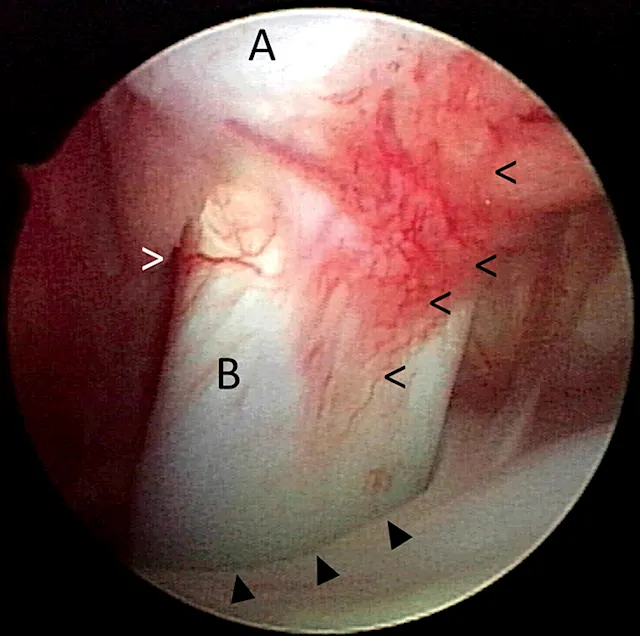

Biceps tenosynovitis is a common cause of forelimb lameness that most frequently affects medium- and large-breed dogs secondary to repetitive fatigue. It is characterized by inflammation of the biceps brachii tendon and the synovial sheath that envelops it in the shoulder joint (Figure 1).1,2 Clinical presentation often consists of a chronic progressive forelimb lameness that is worsened by exercise. The severity of lameness can vary from mild to nonweight-bearing, and atrophy of the supraspinatus and infraspinatus muscles is often present (Figure 2). Pain may be elicited during the biceps test, in which pressure is applied on the biceps tendon in the intertubercular groove when the shoulder is flexed and the elbow extended (Figure 3).1,2 Additional diagnostics (eg, ultrasonography, MRI, arthroscopy) are often needed to confirm diagnosis.1-3 Medical management (eg, rest, NSAIDs, physiotherapy) often results in resolution of mild lesions.1-3 Some dogs may require biceps tendon release or tenodesis to resolve pain and lameness.1-3

FIGURE 1

Arthroscopic image of the shoulder joint of a dog with biceps tenosynovitis. The biceps tendon (B) originates on the supraglenoid tuberosity of the scapula (A) and traverses distally through the bicipital groove of the humerus (closed arrowheads). Synovitis and increased vascularity of the tendon sheath are present (open arrowheads).